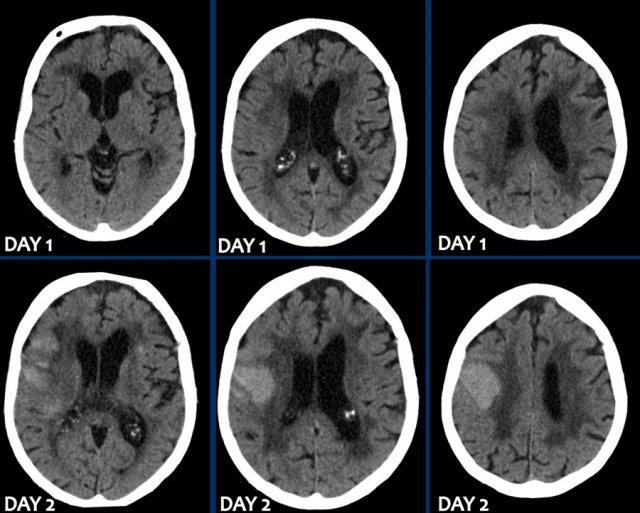

Ba hình ảnh đầu tiên cho thấy khối tụ máu lớn tại hạch nền bên phải kèm phù não lan rộng.

Hình ảnh theo dõi một năm sau cho thấy hình ảnh hang hóa dạng tuyến tính do mất mô (mũi tên) và giảm tỷ trọng hạch nền là hậu quả của xơ hóa thần kinh đệm (gliosis).

Các hình ảnh cho thấy xuất huyết tại hạch nền ở bệnh nhân tăng huyết áp lâu năm.

Tổn thương nằm tại đầu nhân đuôi.

Đầu nhân đuôi nhận máu từ động mạch Heubner và các động mạch thấu kính-vân.

Vỡ các động mạch này gây xuất huyết nhu mô não.

Sự hiện diện của tụ máu trong não thất được coi là yếu tố tiên lượng xấu do tắc nghẽn lưu thông dịch não tủy gây não úng thủy và tăng áp lực nội sọ.